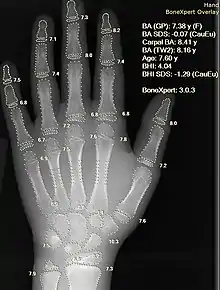

Штучні нейронні мережі використовуються як клінічні системи підтримки прийняття рішень (англ. Clinical decision support system) для медичної діагностики. Наприклад, технологія EMR.

- Комп'ютерна інтерпретація медичних зображень. Такі системи допомагають сканувати цифрові зображення, наприклад, з комп'ютерної томографії, і виявляти типові хвороби. Наприклад, злоякісні пухлини.